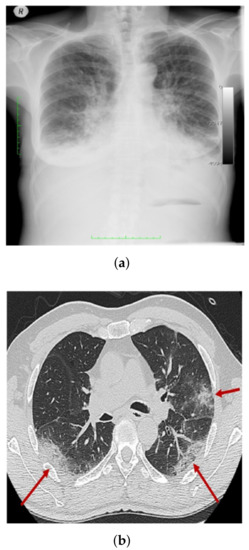

- COVID-19 shows radiological indications that are readily detectable on CXR. As a result, DL-based methods can be used to automatically analyze CXR, significantly reducing the analysis time.

3.1. COV-PEN Image Datasets